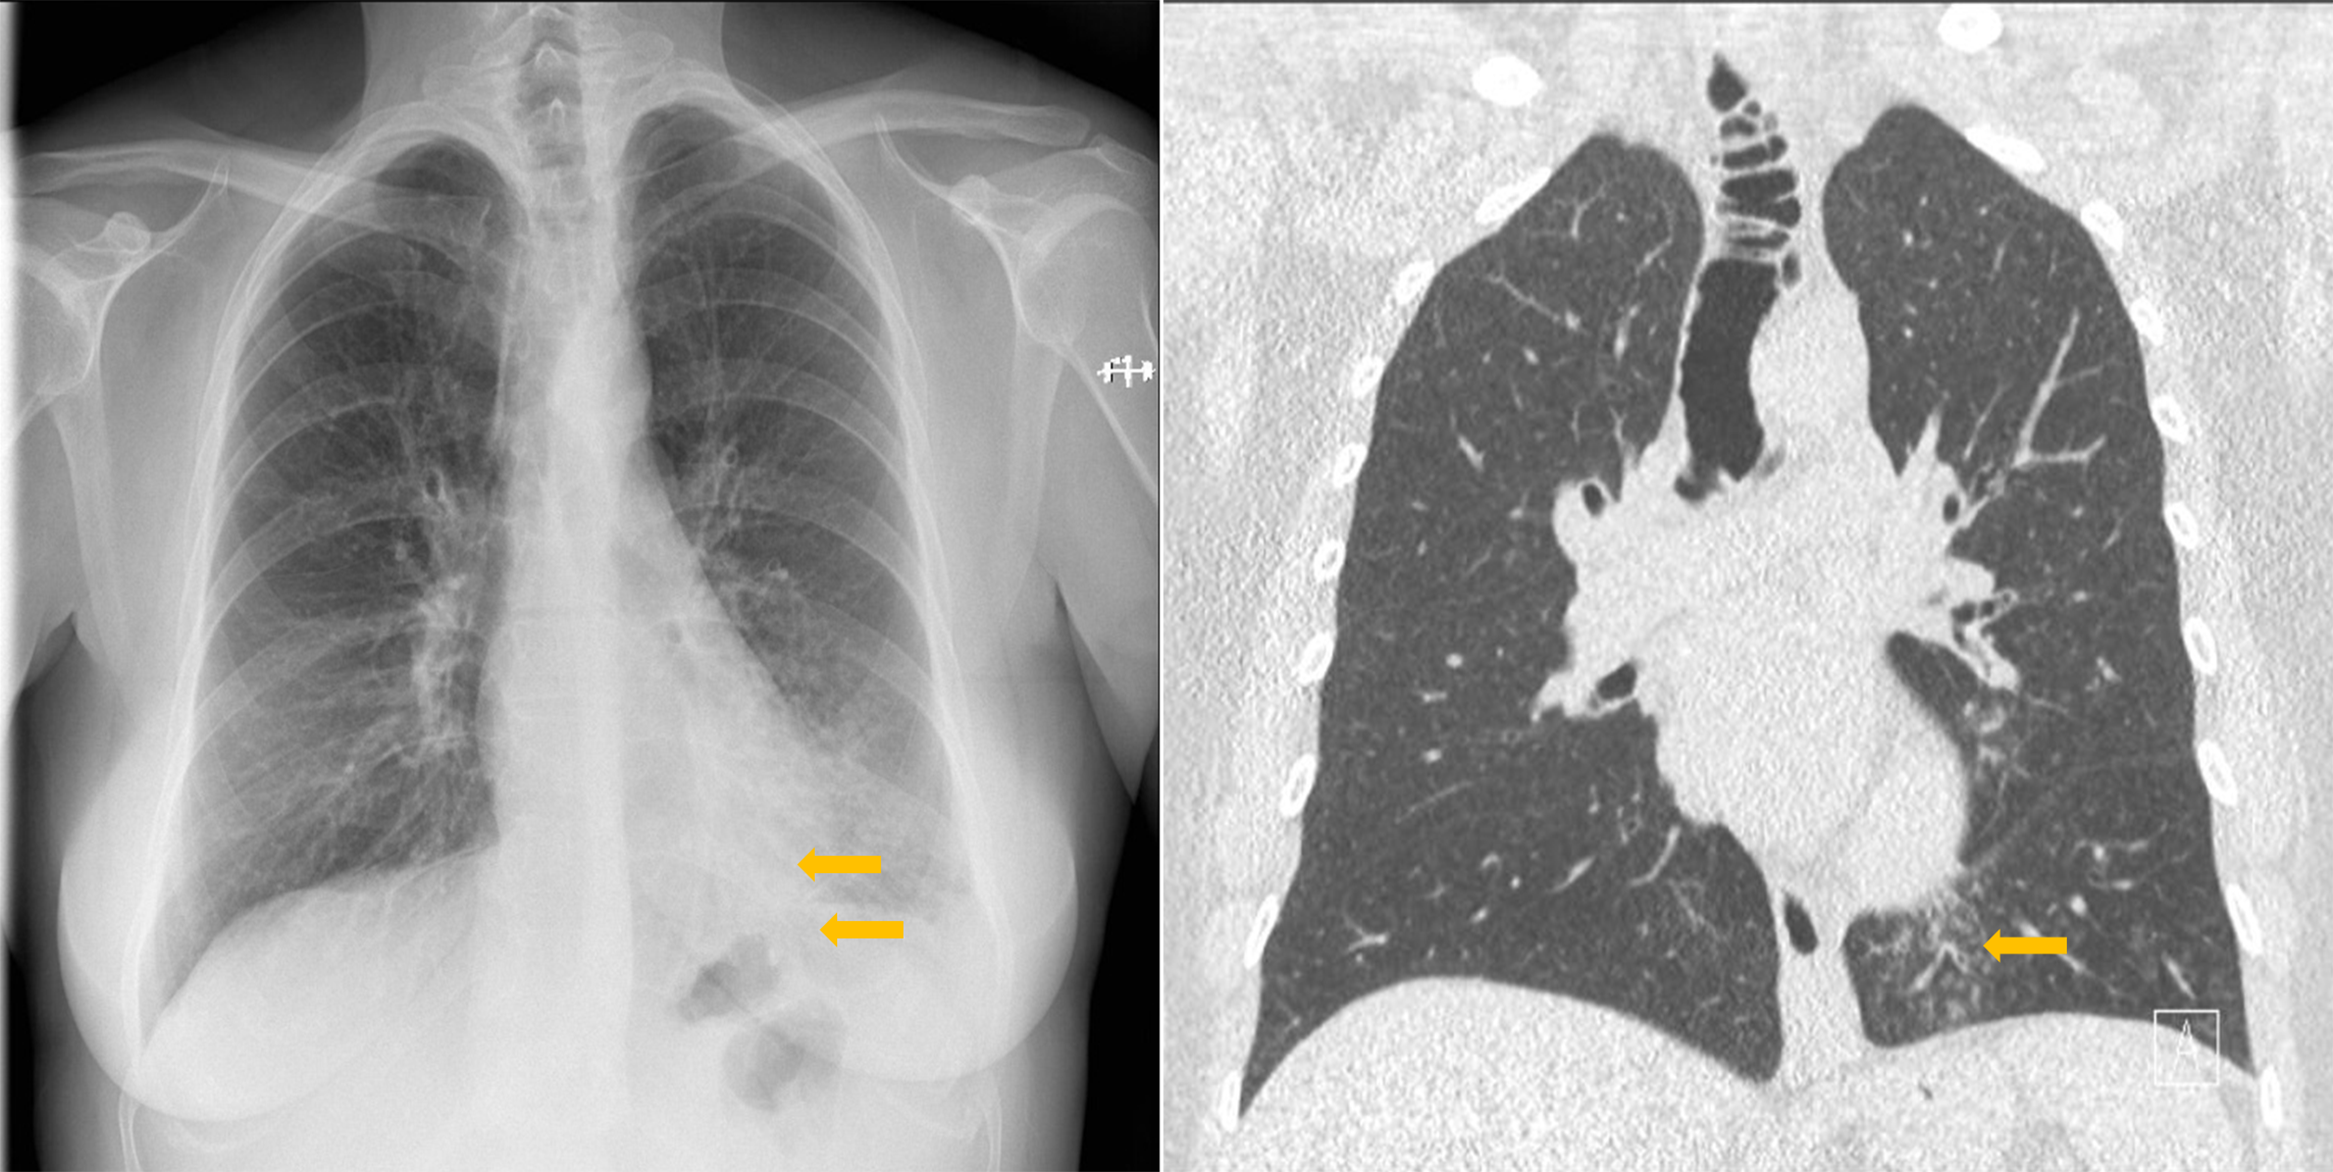

Posteroanterior chest X‑ray revealed blurred small pulmonary nodules scattered over the left lower lobe, suggesting lobar bronchiolitis (Figure 1).

Figure 1

Tracheal diverticulosis and left bronchiolitis; frontal CXR and CT comparison.

After antibiotic therapy for three weeks, a chest computed tomography (CT) examination was performed. Centrilobular nodules with tree‑in‑bud appearance, suggesting inferior lobar bronchiolitis, were still present, but seemed somewhat regressed compared with the initial chest X‑ray. Several tracheal diverticular outpouchings were visible on coronal CT images as well as an increased tracheal size with a maximum transverse diameter of 3.4 cm (Figure 1) consistent with tracheomegaly.